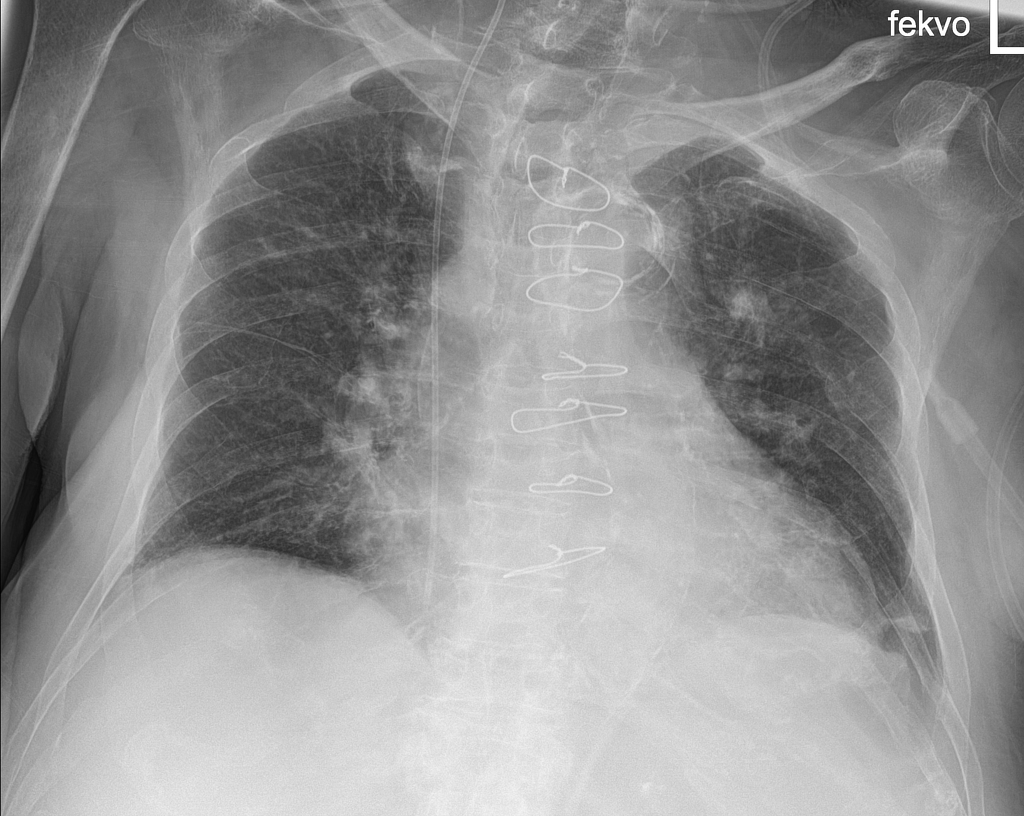

Example 2

Diagnosis

ECG